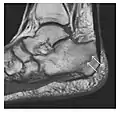

a

b

Figure 7: Fatigue fracture of the talus in a 25-year-old male basketball player with right hind foot and ankle pain, without history of trauma, and a normal initial radiograph (not shown). (a) One-month followup lateral radiograph shows normal appearance. (b) Sagittal T1-weighted MRI shows an irregular fracture line (arrow) within an ill-defined area of hypointensity corresponding to bone marrow edema.[1]